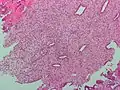

Histopathologic and cytopathologic images.

(A) proliferative endometrium (Left: HE × 400) and proliferative endometrial cells (Right: HE × 100)

(B) secretory endometrium (Left: HE × 10) and secretory endometrial cells (Right: HE × 10)

(C) atrophic endometrium (Left: HE × 10) and atrophic endometrial cells (Right: HE × 10)

(D) mixed endometrium (Left: HE × 10) and mixed endometrial cells (Right: HE × 10)

(E): endometrial atypical hyperplasia (Left: HE × 10) and endometrial atypical cells (Right: HE × 200)

(F) endometrial carcinoma (Left: HE × 400) and endometrial cancer cells (Right: HE × 400).